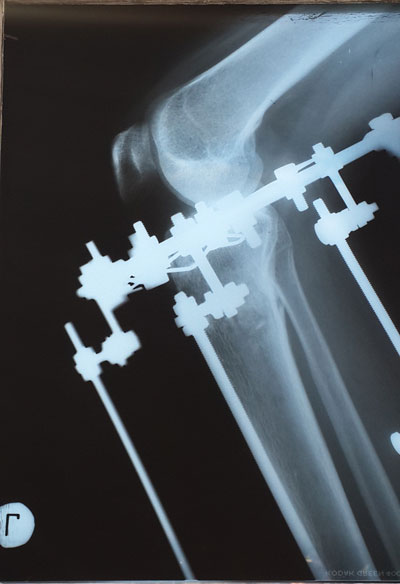

Дата операции 23.01.2015г.

Дата снятия аппаратов 28.04.2015г.

Срок лечения 95 дней.